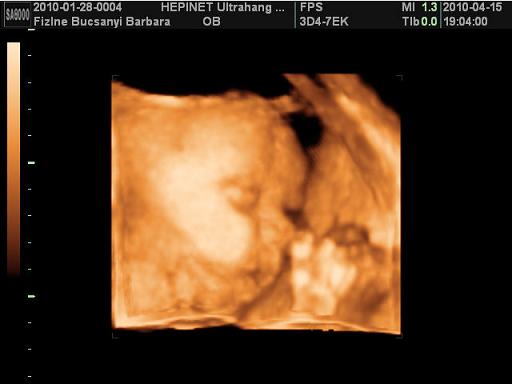

Edi, Bibar: gratu a jó UH-os hírekhez, Kamilláról várjuk ám a képeket, Boti pedig édes kis ManóPofi!